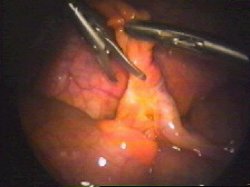

Disección del apéndice

Presentación y colocación de la ligadura

Control de hemostasia